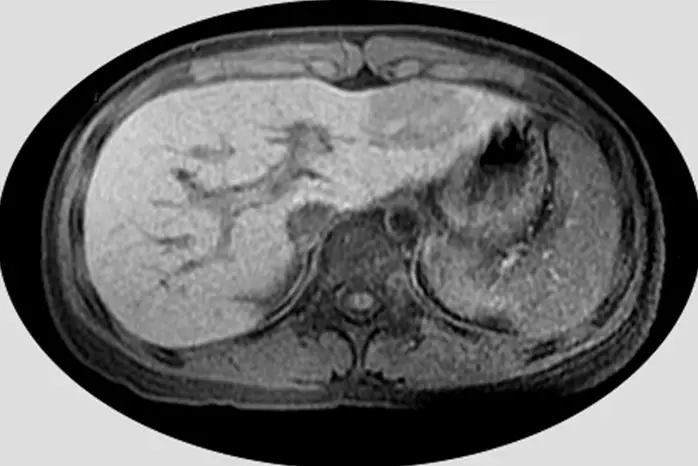

5歲男童因超音波篩檢發現腹部腫瘤,磁振造影 T1 加權影像如圖示,則該腫瘤位於何處?

從所示 axial T1 加權影像可觀察到:

- 正常肝實質呈中等信號強度,較脾臟高;脾臟相對低信號。

- 影像前內側可見一條暗線,對應 ligamentum teres 裂隙(fissure for ligamentum teres),為左內葉(medial segment)與左外葉(lateral segment)之界線。

- 腫瘤位於此暗線(裂隙)之外側,鄰近前腹壁,信號與肝臟實質相近,並不在脾臟所在之區域。

裂隙外側即為左外葉(segments II 和 III),裂隙內側為左內葉(segment IV)。本例腫瘤位於裂隙之外側,屬左外葉範圍。